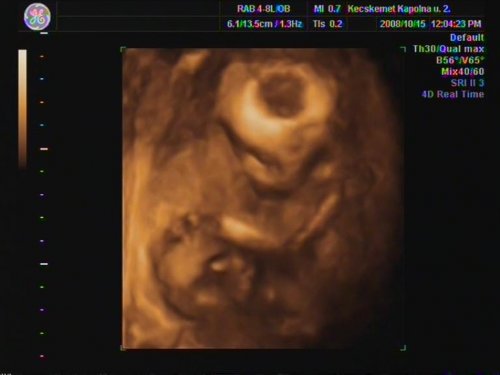

Szóval.................Danikájuk lesz